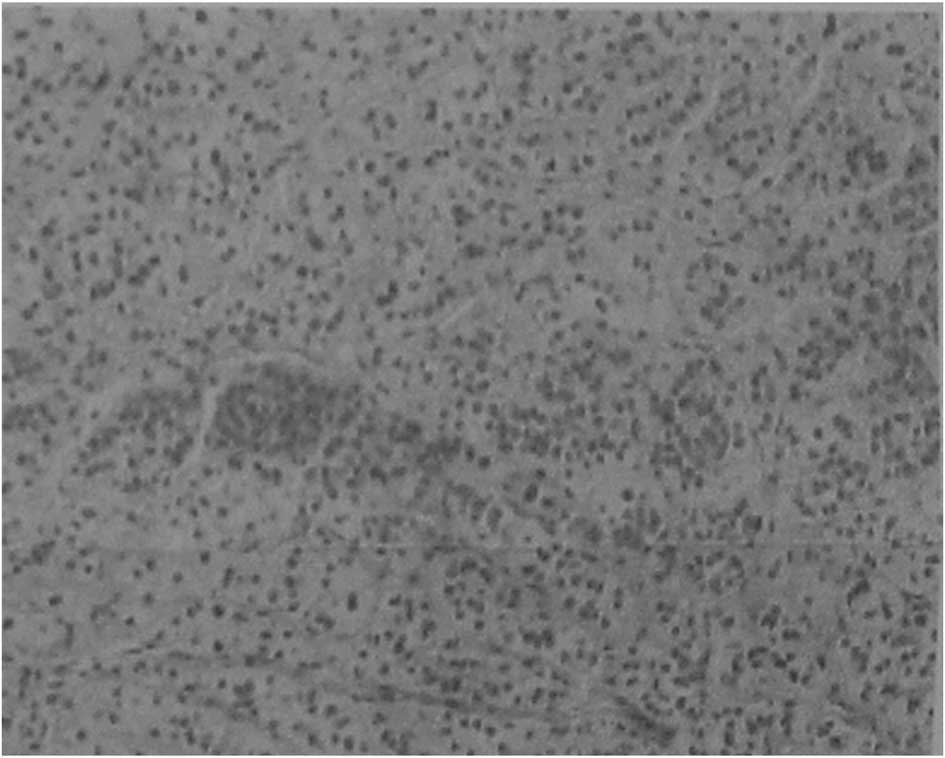

Following surgery, all the resected samples were confirmed positive by histopathological analysis (Fig. 2). The nodules were observed as bright cells under the light microscope and the normal cortical structure had disappeared. The general clinical and biochemical conditions of the patients are summarized in Table II. Lumbar open surgery was performed in nine patients, retroperitoneal laparoscopic surgery was performed in seven patients, single abdominal open surgery were performed in three patients, multiple lumbar open surgery was performed in two patients and laparoscopic surgery was performed in two patients. Infection occurred in one patient following surgery, which was controlled following treatment. The resected adrenal nodular mass in all the patients was a diffused grayish yellow or golden yellow color (Fig. 3). The largest nodular was 6×4×4 cm, weighing 40 g and with no clear coat covering the resected adrenal tissue. The surface of the resected slide was golden brown and had a diameter of 0.6–1.7 cm. Patients with unilateral resection were not treated with hormone drug therapy at discharge; however, bilateral resection patients received 5 or 10 mg prednisone treatment.

Figure 2

Histopathological analysis of the resected adrenal specimen.